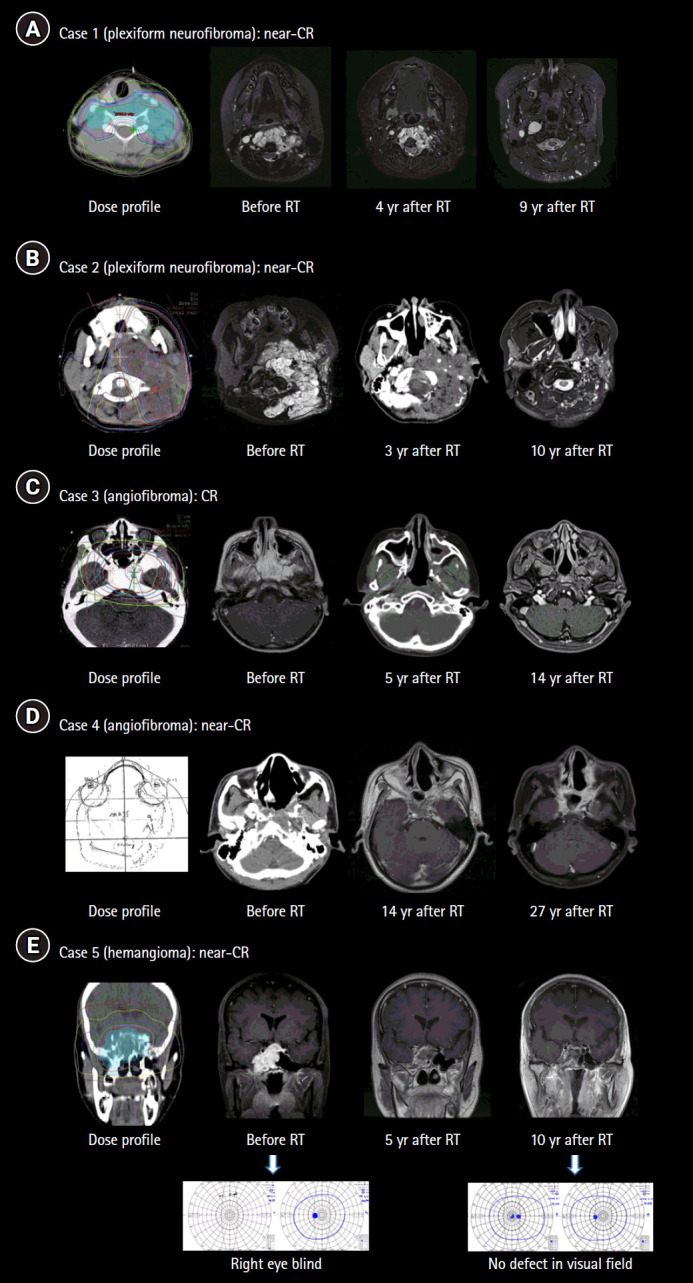

This study aimed to evaluate the long-term efficacy and complication of radiotherapy for benign soft tissue tumors. Five cases of benign soft tissue tumors (two plexiform neurofibromas, two juvenile nasopharyngeal angiofibromas, and one cavernous sinus hemangioma) who underwent radiotherapy were enrolled. All patients had at least 10 years of follow-up. The median follow-up duration was 12 years (range, 10 to 27). Three patients underwent incomplete excision prior to radiotherapy. Radiation doses were either 54 Gy in 30 fractions or 50.4 Gy in 28 fractions (1.8 Gy per fraction). Every patient achieved complete remission (CR) or near-CR. The tumor volume decreased significantly within the first 2 years of follow-up and continued to decrease slowly up to 10 years; no distinct further decrease in tumor volume was observed after 10 years. One patient developed left mandibular hypoplasia 8 years after radiotherapy. Significant volume decrease was achievable within a few years after radiotherapy in benign soft tissue tumors. Therefore, radiotherapy is a viable option for unresectable or incompletely resected benign soft tissue tumors with a minimum risk of complication.

Abstract Image